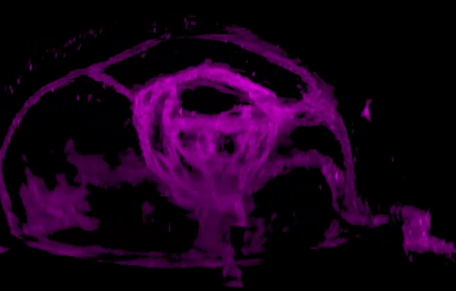

研究人員發(fā)現(xiàn),視網(wǎng)膜干細(xì)胞只能由視泡中間上皮細(xì)胞中一群雙潛能細(xì)胞產(chǎn)生,這群雙潛能細(xì)胞產(chǎn)生視網(wǎng)膜干細(xì)胞的同時(shí)產(chǎn)生視網(wǎng)膜色素細(xì)胞。為深入研究視網(wǎng)膜干細(xì)胞發(fā)育的分子機(jī)制提供了細(xì)胞譜系基礎(chǔ),為最終理解視網(wǎng)膜干細(xì)胞的產(chǎn)生和維持機(jī)制提供可能。

2017年7月26日,西雅圖華盛頓醫(yī)學(xué)院大學(xué)的科學(xué)家們?cè)凇禢ature》上發(fā)表名為“Stimulation of functional neuronal regeneration from Müller glia in adult mice”的論文,在小鼠的眼睛中再生了視網(wǎng)膜細(xì)胞。

雖然小鼠與人類是不同的生物,但是,和人類一樣,小鼠對(duì)于視網(wǎng)膜的損傷也是束手無(wú)策的。然而世間萬(wàn)物總是有一些特別的生物的存在,就像斑馬魚,其視網(wǎng)膜中含有的Müllerglia細(xì)胞攜帶一種能讓它們?cè)偕幕颉狝scl1基因,在視網(wǎng)膜受損后,該基因會(huì)被激活進(jìn)行修復(fù)。

科學(xué)家們通過實(shí)驗(yàn),在成年小鼠眼中再生出了功能正常的視網(wǎng)膜細(xì)胞,這對(duì)于人類視網(wǎng)膜細(xì)胞再生研究十分重要。研究人員表示,他們希望找到其他可以被激活的因子,以使Müllerglia細(xì)胞能再生出所有的視網(wǎng)膜細(xì)胞,這樣就有可能開發(fā)出修復(fù)視網(wǎng)膜損傷的治療方法,讓那些因視網(wǎng)膜受損而失去視力的人重見光明。